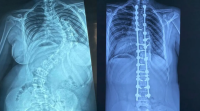

Santo Domingo.– En los últimos cuatro años se han realizado 350 cirugías de deformidades de la columna vertebral pediátrica en la República Dominicana, distribuidas entre el Hospital Infantil Robert Reid Cabral y la Sociedad Dominicana de Rehabilitación, bajo la coordinación del doctor Carlos Rodríguez Estévez. (Sigue leyendo…)